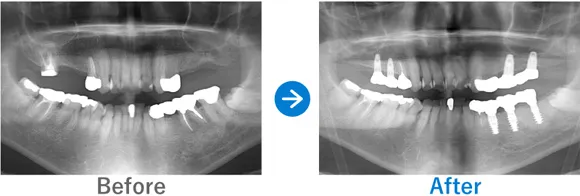

ほぼ虫歯な状態から、できるだけ歯を残した最小限のインプラントできれいな口元に

全顎ランパントカリエス(複数の歯に同時に虫歯が発生する状態)

インプラント4本:上顎2本、下顎2本、残せる歯はすべて補綴治療

4,917,000円(内訳:抜歯テルプラグ、GBR、根管治療、インプラント4本(ストローマン)、ガイド、全顎仮歯、補綴治療、セデーション、保証20年)

※当時の価格で現在とは異なる場合があります。

来院の背景

歯医者が苦手で、子供時代に歯科にかかったきりでした。ほとんどの歯に虫歯がある状態だったため、心配になったお父様が連れてこられました。

治療結果

まだお若いため、残せる歯はできるだけ残したうえで補綴治療(クラウンやブリッジなどによる治療)を行い、どうしても抜歯が必要な歯4本のみインプラントを行う方針で治療を進めました。

治療後は、見た目が整ったことはもちろん、しっかり噛めるようになったと喜んでいらっしゃいました。歯磨きが苦手とのことなので、定期メンテナンスでのアフターフォローも大切です。